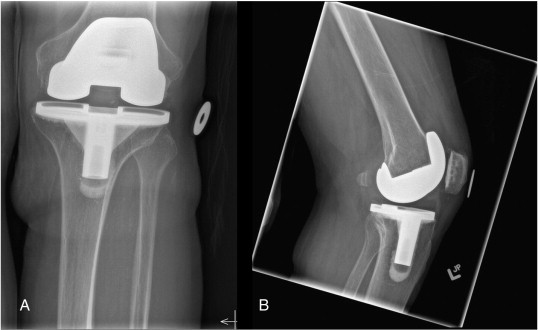

18

Q

Patient had undergone right knee TKA 12 years ago, now complaining of sudden onset pain at the operated knee on ambulation. This is the plain radiograph of the symptomatic knee.

1. Describe the plain radiograph.

2. How will you investigate this patient to arrive to your clinical diagnosis?

3. What is the cause of this patient’s symptoms?

4. How will you manage this patient’s pain?

A

1. Plain radiograph

Right knee prosthesis is subluxed

Evidence of femoral and tibial osteolysis

• Tibia AP - > 2 mm radiolucent area beneath the tibial plate and cement interface.

• Femoral Lat - > 2 mm radiolucent area in the posterior condyles between femoral component and cement interface.

Change in position of implant - tibial component has flexed and varus subsidence.

** cement cracking/fragmentation and delamination

1. IX - ESR and CRP to rule out infection

Clinically- afebrile, no local signs of infection (erythema, warmth, tenderness), only minimal pain on ROM and increased pain on weight bearing.

1. Aseptic loosening of TKA prosthesis

2. Revision TKA

if bone defects > 10 mm

+ prosthetic metal wedges/augments (if elderly, inactive)

+bone graft (younger patients, active)

Re picture attached:

The classic loosening of the implant in worst instances begins with a delamination pull-away of the cement on the posterior keel, followed by failure of the proximal posterior tibial surfaces; Compare the positioning immediately post-op (a) verses that at 6 months, where the slope changes from 7o to 9o and the implant subsides (b)

https://jeo-esska.springeropen.com/articles/10.1186/s40634-020-00243-9